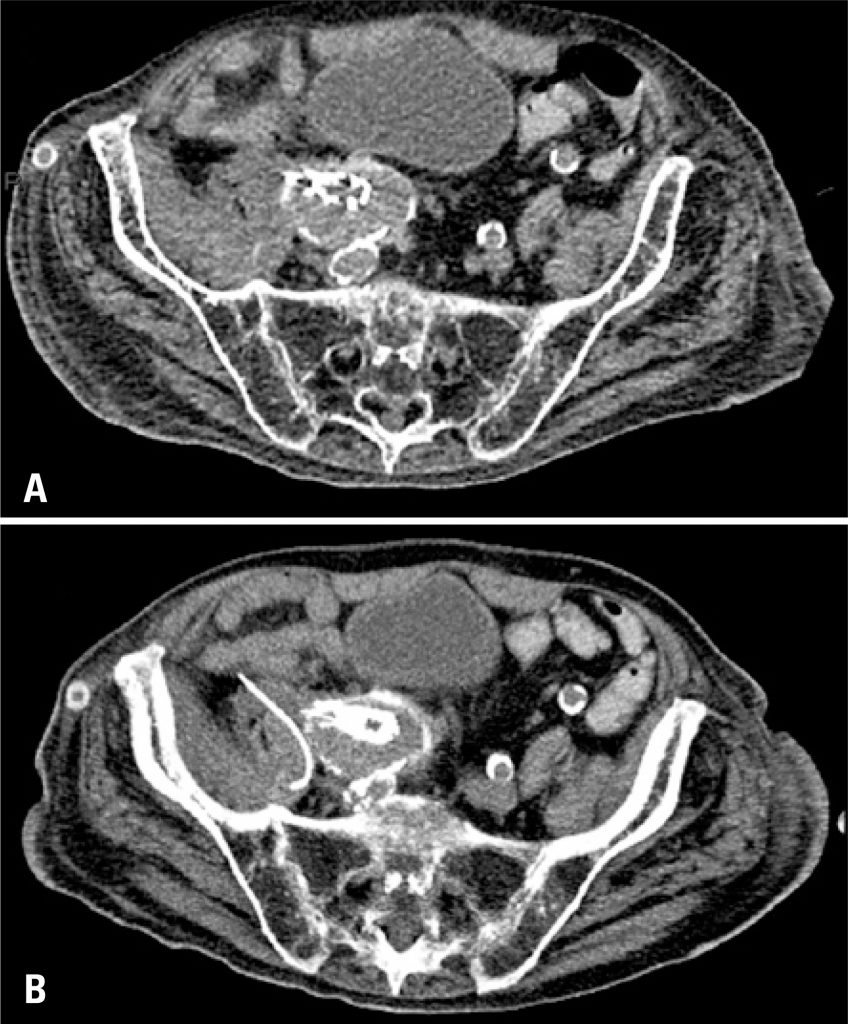

Endovascular aneurysm repair is an established technique for treating many infrarenal aortic aneurysms. Infection is one of the most serious complications of this technique, and although percutaneous treatment has been well established for intra-abdominal collections, its use to treat peri-prosthetic fluid collections has not been well determined. In this article we describe a small series of three patients who were treated with percutaneous drainage, with good clinical and imaging responses. Percutaneous drainage is a safe, effective and minimally invasive approach for treating this potentially fatal complication.